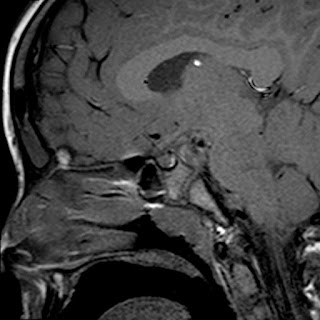

Caso neurorradiología

Paciente de 60 años con cuadro de 1 semana de evolución consistente en tropiezos frecuentes y alteración en la movilidad del miembro

inferior derecho. No refiere

cefalea u otros síntomas asociados, no pérdida de peso, no náuseas o emesis, no

sudoración nocturna. Antecedentes de hipertensión arterial y diabetes.

Resonancia magnética